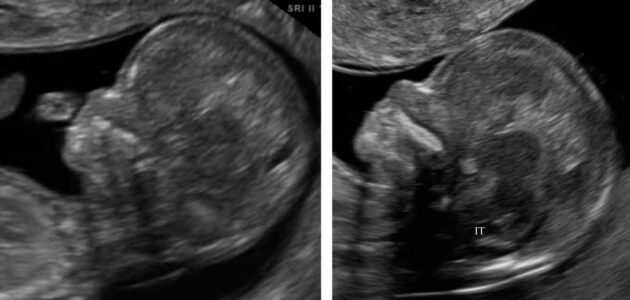

نشانه همبرگر=جنسیت دختر

زمان انجام آزمایش سونوگرافی جهت تشخیص جنسیت جنین، فرد آزمایش گیرنده به دنبال ناحیه ژنیتال، لابیا و کلیتوریس دختر می باشد.

نشانه لاک پشت= جنسیت پسر

زمانی که در آزمایش اولتراسوند به دنبال جنسیت پسر هستند به دنبال نشانه به اصطلاح لاک پشت می باشند. حالتی که که سر آلت تناسلی از بیضه ها بیرون می زند شبیه به لاک پشت می باشد. در برخی از موارد مشاهده این مورد در پسران مشکل می باشد به این دلیل است که به دنبال نشانه های چندگانه ای برای تعیین جنسیت می گردند. موقعیت جنین و سن دقیق بارداری نقش مهمی در تشخیص جنسیت بازی می کنند.